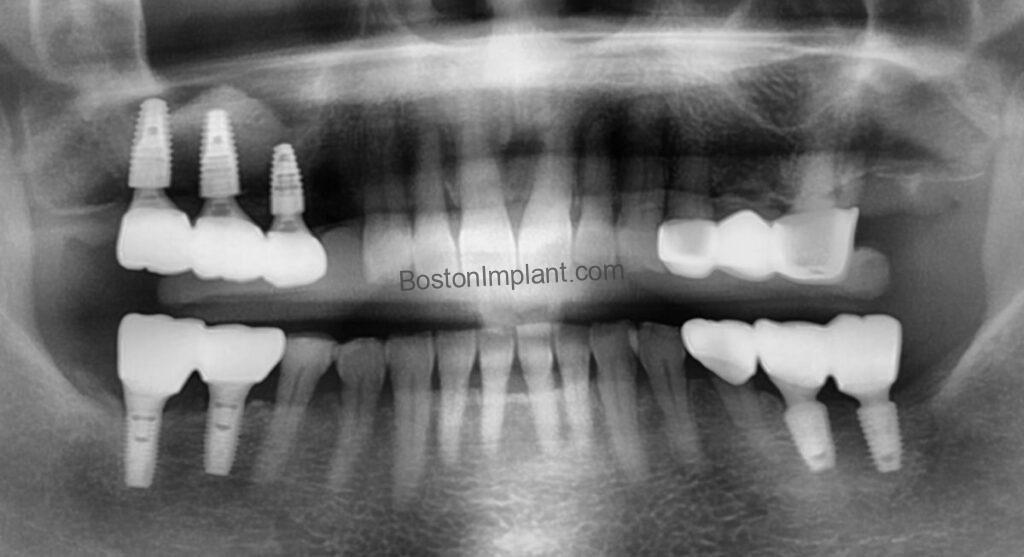

Through comprehensive 3D CBCT planning and precise surgical technique, we successfully completed the sinus graft without complication.

A Conservative Alternative: The Upper Left Bridge

While we planned seven implants for the right side, our approach to the upper left side was different. The patient had a second premolar with poor periodontal health and a first molar with slight bone loss.

Rather than extracting these teeth and placing more implants, we chose a dental bridge. Our philosophy is simple: Your natural teeth are precious. Whenever we can safely stabilize and save a natural tooth, we prioritize that over an extraction.

Efficiency in Treatment: The “Fast-Track” Timeline

Sinus grafts require patience—typically 6 months for the bone to fully mature and integrate. To ensure the patient didn’t have to wait half a year to eat comfortably, we designed a staged treatment plan:

1. Phase 1: Perform the sinus graft on the upper right.

2. Phase 2: We placed implants in the other areas—the upper left and both lower sides—where the bone was sufficient and did not require complex grafting.

3. Phase 3: Restore the areas first so the patient could regain chewing function quickly on left side.

4. Phase 4: Once the graft matured, place and restore the final implants in the sinus area.

The Result

By working efficiently and staging the procedures, we minimized the total treatment time and maximized the patient’s comfort. Today, she has regained full functional ability and a confident smile.